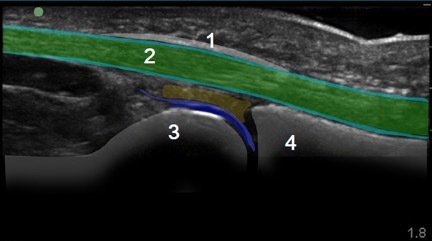

Hand Flexor Tendon 1 Image

A1 Pulley

Flexor Tendon

Distal Metacarpal Head

Proximal Phalanx